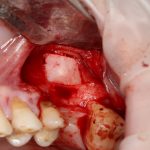

Возвращаемся к основной операционной области. Еще раз посмотрим на альвеолярный гребень, поофигеваем от его ширины и моих грандиозных планов:

Глянем на то, что получилось:

Осталось адаптировать костный блок (убрать острые края), проверить его фиксацию и, при необходимости, добавить винты. Десятисекундное дело.